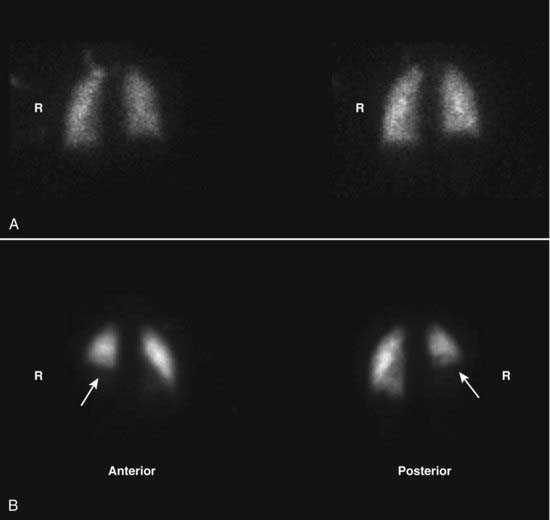

imagePulmonary emboli should produce a segmental mismatch on the V/Q scan in which ventilation is maintained but perfusion is absent. Depending on the number and size of defects, correspondence between the ventilation and perfusion scans and the appearance of the chest radiograph, the results of the lung scan are categorized as being normal, low, intermediate, or high probability for pulmonary embolism (Fig. 13).

image

Figure 13 Pulmonary embolus on ventilation/perfusion (V/Q) scan.

A, The ventilation scan is normal. B, A large photopenic defect is seen at the right lung base (white arrows) on the perfusion scan. There is a mismatch between the ventilation and perfusion scans since the abnormality is present on one but not the other. Pulmonary emboli should produce a segmental mismatch like this on the V/Q scan in which ventilation is maintained but perfusion is absent.